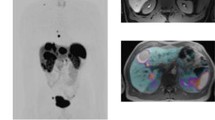

Simultaneously acquired, fused magnetic resonance-positron emission tomography (MR-PET) imaging after injection of fluorine-18 fluorodeoxyglucose (18F-FDG) (a) and 11C- Pittsburgh compound B (PiB) (b) in a 68-year-old male patient having increasing declining memory performance during the last 3 years with development of stuttering speech and slow gait. Since 8 months, the patient developed visual and acoustical hallucinations, too. FDG-PET revealed decreased glucose metabolism in the parieto-temporal and occipital cortex including the visual cortex, whereas increased FDG-metabolism was observed in the basal ganglia. Non-pathological amyloid-β deposition thus excluding Alzheimer disease was shown on Pittsburgh compound B (PIB)-PET scan. After MR-PET imaging, the patient was diagnosed with Lewy body dementia